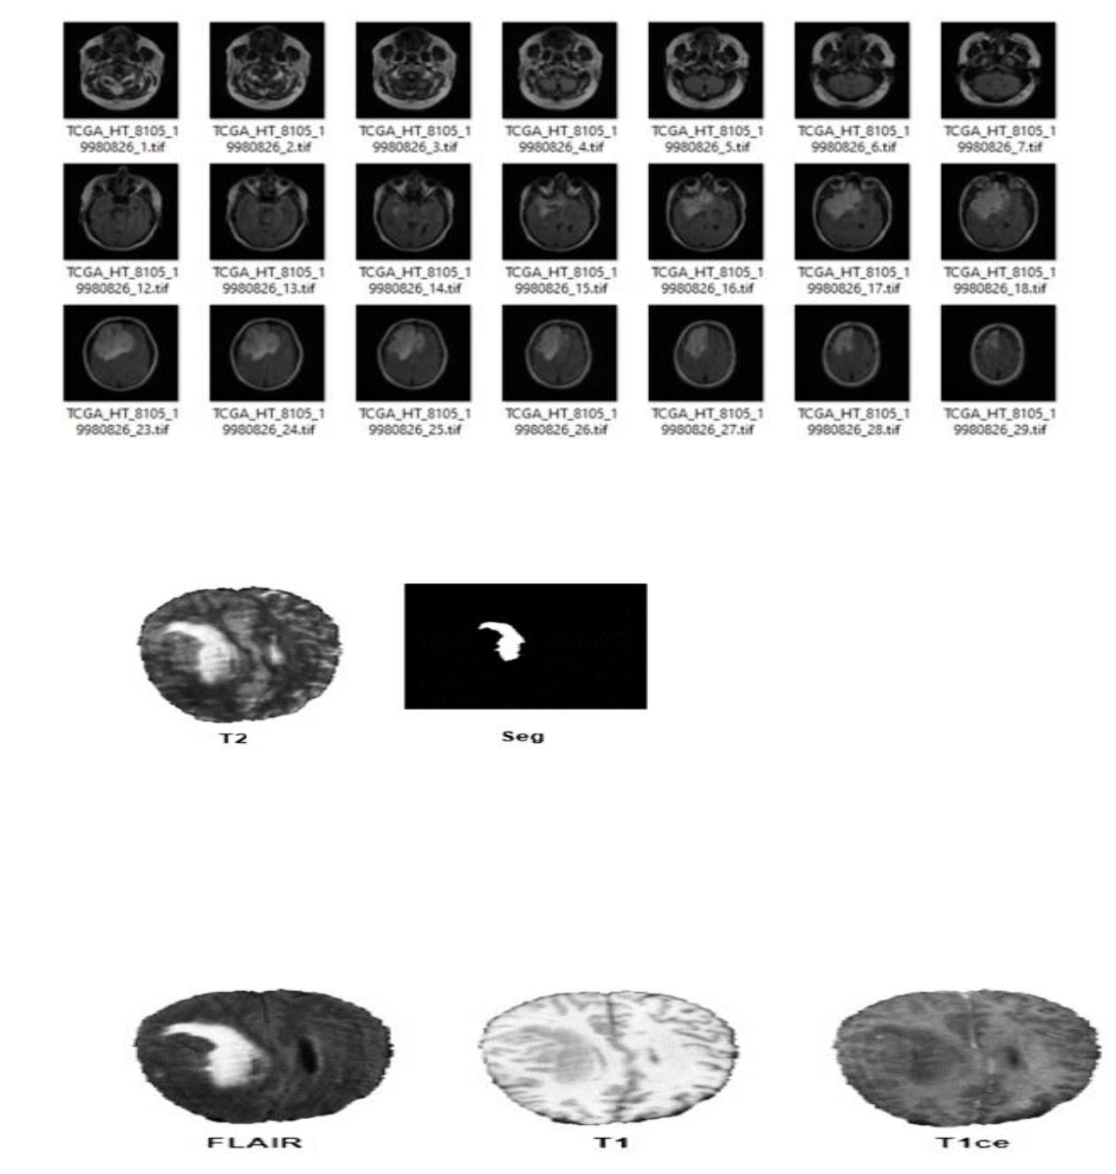

The BraTS2019 dataset is a widely used public resource featuring 335 multi-modal 3D MRI scans from various clinical centers. Each scan includes five imaging types: FLAIR, T1-weighted, T1-weighted with gadolinium contrast (T1ce), T2-weighted, and a manual tumor segmentation mask. Of these 335 scans, 259 are from patients with aggressive High-Grade Gliomas (HGG), and 76 are from patients with less aggressive Low-Grade Gliomas (LGG), representing the typical clinical ratio.

Each MRI modality highlights different aspects of the tumor. FLAIR highlights swelling and abnormal tissues by suppressing fluid signal, while T1 provides detailed anatomical structure. T1ce reflects tumor regions with active blood-brain barrier disruption through contrast enhancement. T2 shows non-enhancing and cystic tumor areas. The segmentation masks, expertly annotated by radiologists, distinguish tumor presence versus healthy brain tissue. Fig. 4 shows a sample of the Dataset: